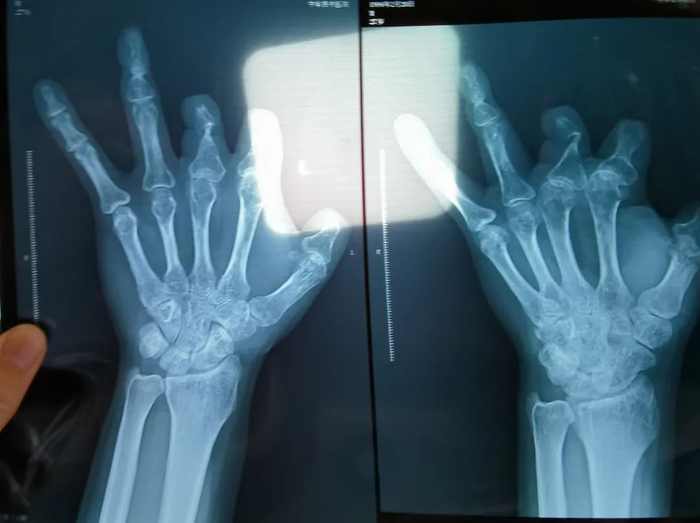

收费记录显示,彭先生术中使用了6个微血管吻合装置,共计100800元,然而X光片却表明,这6个“不可降解、吸收”的进口器材,一个都不存在于他体内。

1月5日,郑州中牟县患者彭先生向新京报记者反映称,2017年11月,他不慎切伤左手,到郑州大学第一附属医院(以下简称“郑大一附院”)手术,收费记录显示,术中使用了6个微血管吻合装置,共计100800元,然而X光片却表明,这6个“不可降解、吸收”的进口器材,一个都不存在于他体内。

▲彭先生后期拍摄的X光片显示,未见一个微血管吻合装置。新京报记者 程亚龙 摄

1月5日,彭先生再次到中牟县中医院拍摄X光片,显示其体内未见微血管吻合装置。此前,多名医疗行业从业者及微血管吻合装置的厂家工作人员称,该器材“由超高分子量聚乙烯和不锈钢针组成,不可降解、吸收,使用后X光片中会有显示”。